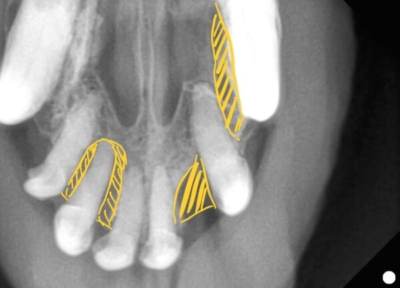

上顎切歯

上顎の切歯のレントゲン

黄色斜線部分が歯の周りの骨が溶けてしまったところ。

このようにひとつひとつの歯を評価していきます。